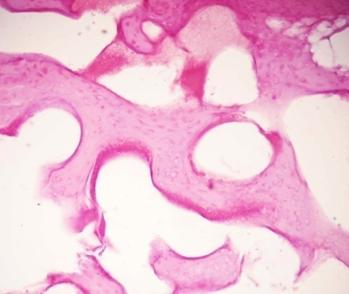

Через 6 мес. гистологическая картина в области установки никелид-титанового имплантата характеризовалась формированием в области дефекта элементов губчатой кости. При микроскопическом исследовании, наряду с плотной оформленной соединительной тканью, имеющей толстостенные питающие артерии, полнокровные вены, определялись участки хрящевидной ткани неправильной формы, местами подвергающиеся обызвествлению. Дистрофически измененные хрящевые клетки были расположены параллельными рядами, формируя так называемые зоны «столбчатого хряща» с мелкими очагами обызвествления, в непосредственной близости к ним находились формирующиеся костные трабекулы. Новообразованные костные балки имели на продольных срезах неправильную форму, слабо базофильную окраску основного вещества, в котором были заключены отдельно расположенные остеоциты (рис. 10, 11). На поперечных срезах костные балки были представлены концентрически расположенными пластинками, формирующими остеоны, в центре которых определялись каналы для прободающих кость сосудов (рис. 8).

Рис.8. Зона «столбчатого хряща» (ЗСХ), формирующиеся костные трабекулы (указаны стрелками) через 6 месяцев после пластики пористо-проницаемым мелкогранулированным никелидом титана в области дефекта. Окраска

гематоксилином и эозином. Увел. 150

Рис. 9. Новообразованные костные балки через 6 месяцев после пластики пористо-проницаемым мелкогранулированным никелид-титаном в области дефекта.

Окраска гематоксилином и эозином. Увел. 150

Рис. 10. Формирование остеонов: концентрически расположенные костные пластинки (указаны стрелками), каналы остеонов (КО). Поперечный срез новообразованной кости через 6 мес. после пластики пористо-проницаемым мелкогранулированным никелидом титана в области дефекта. Окраска гематоксилином и эозином.

Увел. 400